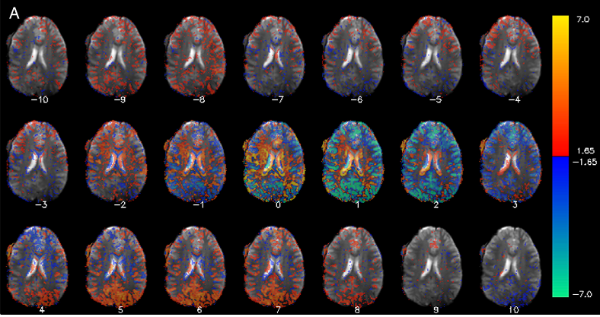

The functional MRI Facility (FMRIF) is a core resource serving the Intramural Research Program. It was initiated in 1999 primarily by the National Institute of Mental Health (NIMH) and the National Institute for Neurological Disorders and Stroke (NINDS). Its function is to serve as a resource by which all NIH institutes can perform Magnetic Resonance Imaging (MRI) studies that further the understanding of healthy and diseased brain anatomy, function and physiology.

The Facility provides a complete environment for stimulus presentation, monitoring and recording subject behavior and physiology while performing functional MRI (fMRI). At present, the Facility has a total of five scanners for the investigation of humans. These scanners consist of 2 General Electric 3 Tesla MRI scanners, one Siemens 3 Tesla MRI scanner, and 2 Siemens 7 Tesla MRI scanners. More information about each of these scanners and the peripheral user devices equipped can be found here.

The staff of the FMRIF continues to be committed to maintaining a world-class fMRI scanning environment, providing capability for exploring brain function, physiology, and morphology in healthy volunteers and clinical populations.